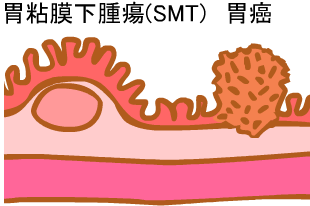

| ”S–Œ‰؛ژîل‡(SMT) |  |

|

|

| ڈ\“ٌژw’°’×ل‡ | ڈ\“ٌژw’°SMT |

| ڈ\“ٌژw’°ٹàپi‚ك‚¸‚炵‚¢ڈا—ل‚إ‚·پj | “¯ڈا—ل‚جNBI‰و‘œپiژîل‡ŒŒٹا‹’²ژB‰eپj |